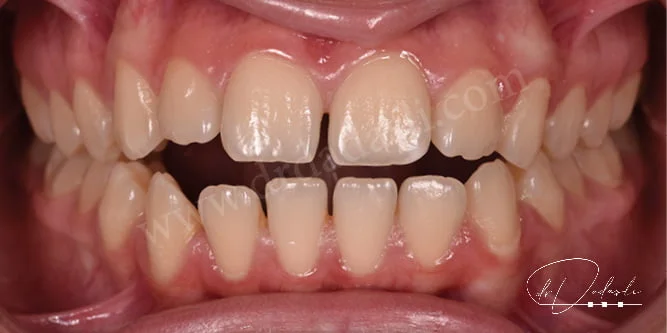

- Boşluklar (Şekil 8 ve 9) – dişler arasında bir veya daha fazla boşluk varsa, kapatılması için ortodontik tedavi yapılmalıdır.